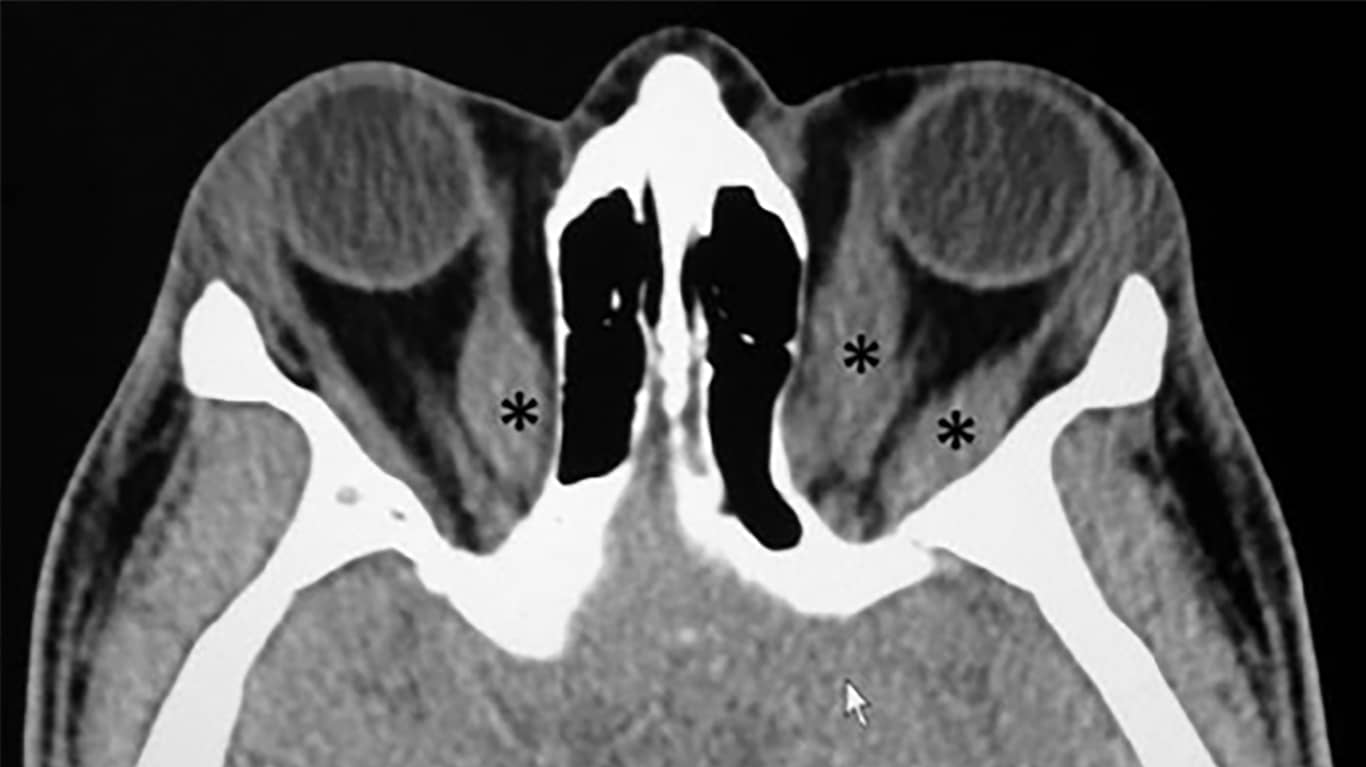

آزمایش های دیگری که پزشک شما ممکن است درخواست کند عبارتند از: سونوگرافی چشم / توموگرافی کامپیوتری (CT) / تصویربرداری رزونانس مغناطیسی (MRI)